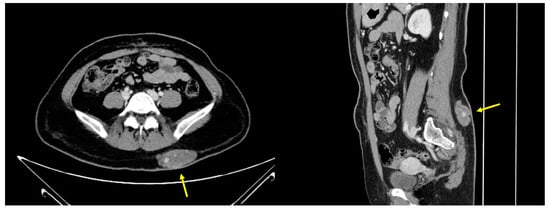

2.6. Imaging Examination